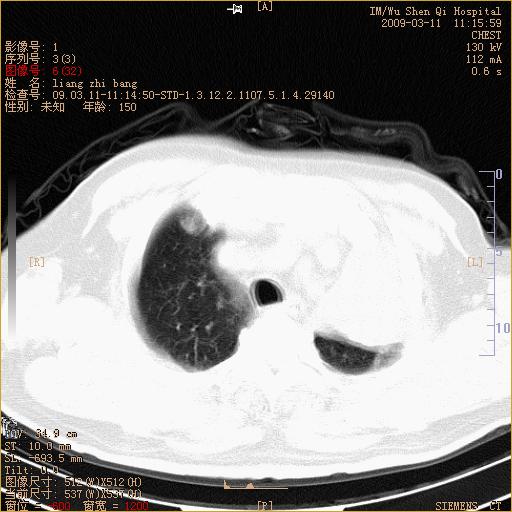

标题: CT18604:男,60岁,咳嗽一月余 [打印本页]

标题: CT18604:男,60岁,咳嗽一月余

1)考虑左肺上叶中央型肺癌并左肺上叶肺不张;建议必要时行纤支镜检查进一步明确诊断。2)左侧胸腔积液。

1、左肺上叶中央型肺癌并上叶阻塞性肺不张。

2、左侧胸腔少量积液,右侧胸膜轻度增厚。

左肺们肿块并左肺上叶不张。考虑左肺中心性肺癌并左肺上叶不张及左侧胸腔积液